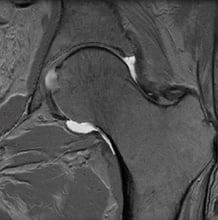

MRI of a normal hip with an intact labrum